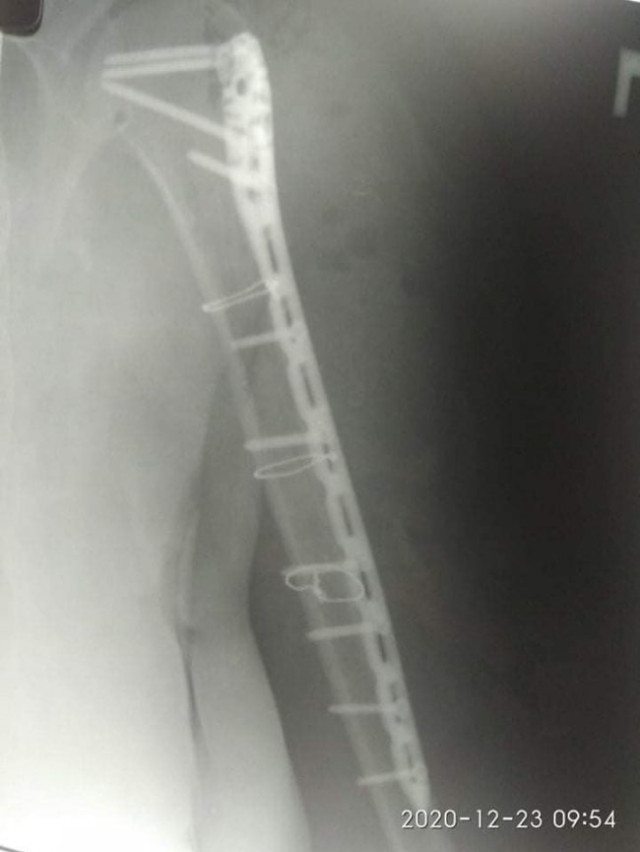

21 грудня їй провели 4-ьох годинну операцію – остеометалосинтез правої плечової кістки за допомогою LCP проксимальної Philos пластини та гвинтів.

Операція пройшла у складі лікарів-травматологів: Лотоцького І.А., Радчука В.М, Босого Т.Б..

Завдяки вчасно проведеній операції пацієнтка уже знаходиться у задовільному стані та готується до виписки.